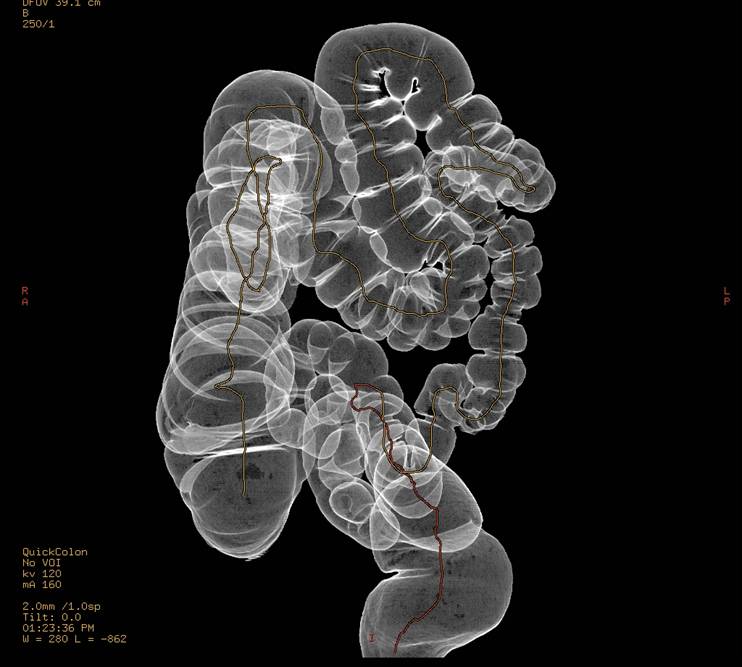

3D fremstilling af normal tyktarm i forbindelse med CT-kolografi.